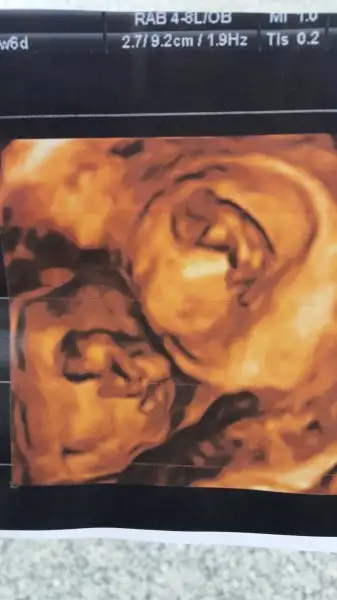

Sabah doktora gitmiştik..

Önceki kontrolde hiçbişi anlamamıştım ama bu sefer her şeyi daha iyi idrak ettim ve aşırı mutlu oldum..

İki tane kıpır kıpır elleri kolları kımıl kımıl kuzu gördük.

O kadar güzellerdi ki.

Doya doya ekrana bakmaktan gözlerimi alamadım..

Bunlar benim kuzularım

İkisi de aynı gidiyor 9+4'ler :)

Ben kendim rica ettim dedim ikisini bir alan bi resim istesem dedim dur aynı açıdan yakalamaya çalışayım dedi bunları verdi çok mutlu oldum :)ya çok güzeller ben ilk kese fotosunu istemeyi unuttum tahlil yapıp geldiğimde istedim kaydetmiyoruz diyip vermediler